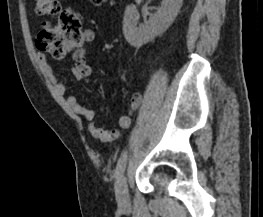

Мультиспиральная компьютерная томография позволяет детально оценить структуру лимфатических узлов, выявить ее неоднородность, определить точные размеры, выявить деформацию контуров, появление инфильтрации окружающих тканей с образованием цепочек, пакетов и конгломератов лимфоузлов.

Мультиспиральная компьютерная томография позволяет оценить структуру лимфатических узлов, обнаружить неоднородность, гиперплазию, деформацию их контуров.

Мультиспиральная компьютерная томография дает возможность визуализировать размеры лимфоузлов, их точную локализацию, взаимодействие с близлежащими органами и окружающими тканями, образование спаянных между собой инфильтратов лимфоузлов, выявить прорастание в окружающие ткани.